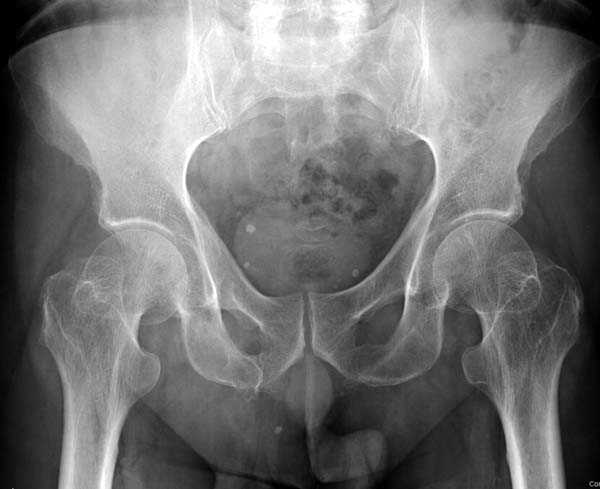

неполный перелом шейки

в течение первых 72 часов после перелома, остеосинтез тремя спонгиозными шурупами.

Почему неполный перелом? Я бы назвал его вколоченным!

Перелом конечно не вколоченный т.к. видно линию перелома и нет суперпозиции костной ткани.

Добрый день. Перелом коварный. Через время может произойти лизис в области "неполного" перелома и он превратиться в "полный" со всеми очевидными проблемами, тем более у пациента, склонного к питию. Если не разовьется делирий или после выхода из него, рекомендую внутренний остеосинтез винтами.

Профилактику дальнейшего раскола неполного перелома шейки провели тремя канюлированными шурупами.